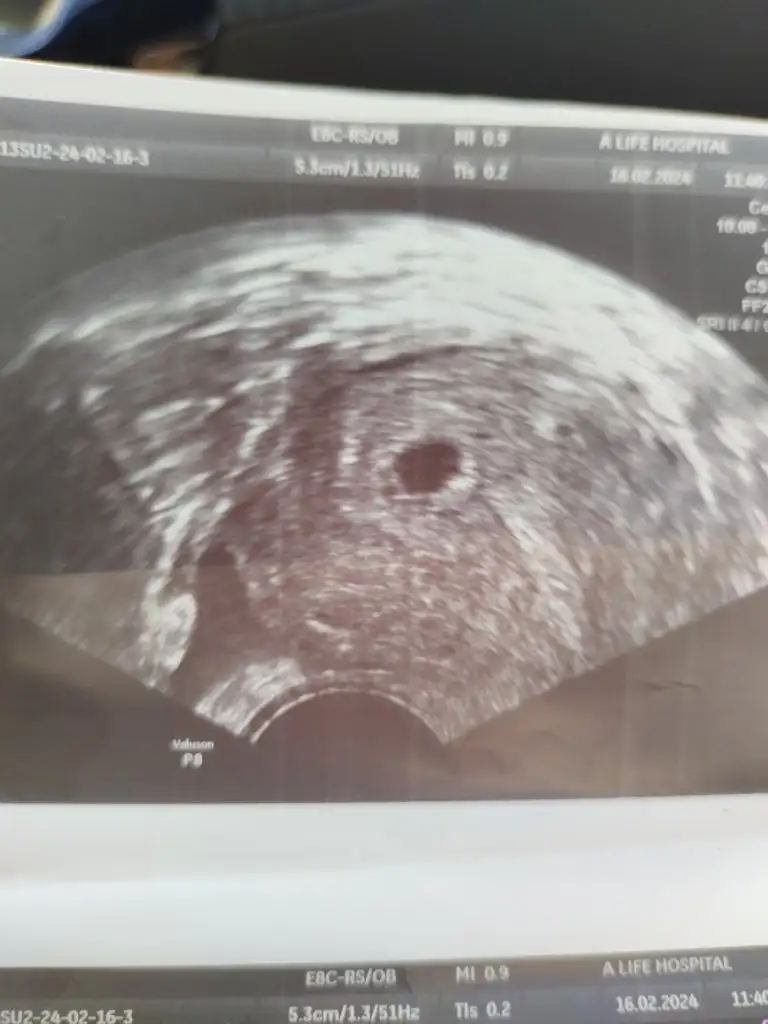

Son adet tarihim 04.01.2024

Yumurtlama 04.02.2024

Beklenen adet tarihim de 18.02.2024 idi.

Direncli bir polikistik yapım var.

16.02.24 tarihinde Standart kaset test kullandım ve ikinci çizgiyi silik gördüm. 4 saat sonra predictor marka erken gebelik testinde ikinci çizgi cok net belirginlesti. Dün akşam kan verdim. Beta hcg sonucum 108 çıktı fakat doktor karın üstünden baktığı ultrasonda "rahim icinde bir sey yok henüz ama rahim kalinlasmis, bebegi bekliyor." dedi. Eğer her sey yolunda giderse sanırım ben de aranıza katıldım. :)